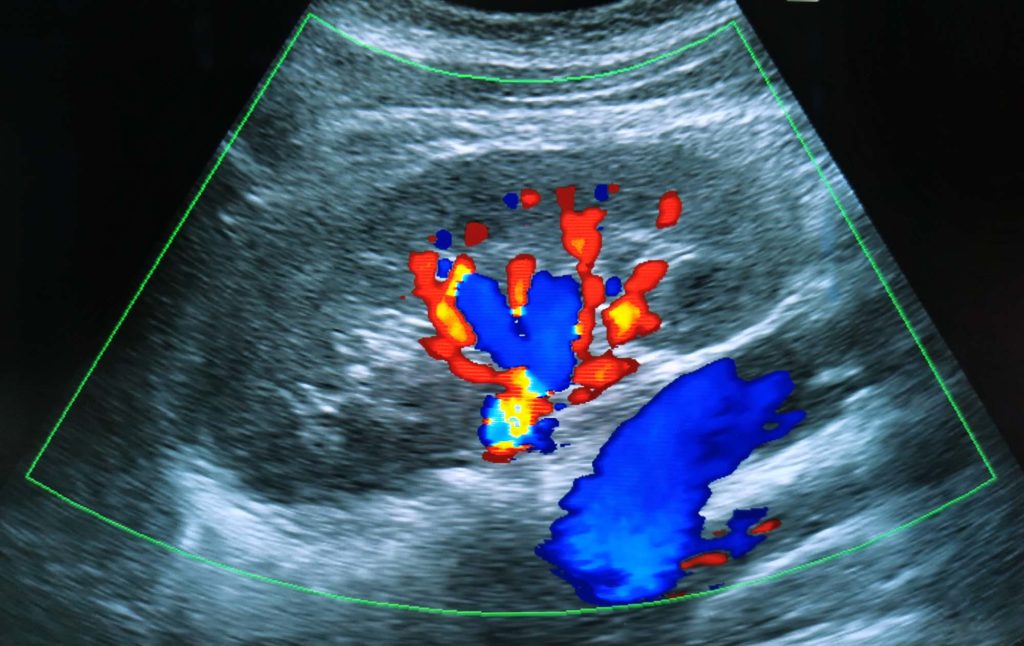

Renal artery ultrasound is a non-invasive imaging technique used to visualize the blood flow in the renal (kidney) artery. On the other hand, abdominal aortic ultrasound is a safe and fast procedure used to measure the size of the abdominal aorta, which is the main artery in the body. Both of them can help diagnose blockages or irregularities in the artery, as well as other problems such as aneurysms and stenosis.

During a renal artery ultrasound, a device called a transducer is used to create an image of the kidney and its blood vessels. During an abdominal aortic ultrasound, sound waves are used to detect narrowing or aneurysms of the aorta. Both procedures usually take about 20–30 minutes.